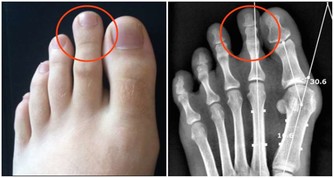

痘痘的影響 痤瘡俗稱為青春痘,它總會在你毫無防備的情況下襲擊你的臉龐。它其實是由於皮脂腺分泌過多油脂,加上毛孔內毛髮和老死角質的堆積,使油脂和細菌附著,引發皮膚紅腫的反應。其常見於青少年,但近些年成人痘也成為不容輕視的皮膚問題。青春痘一旦處理不當留下痘印痘疤就會對外貌造成嚴重影響。

痘痘、痘印產生的過程